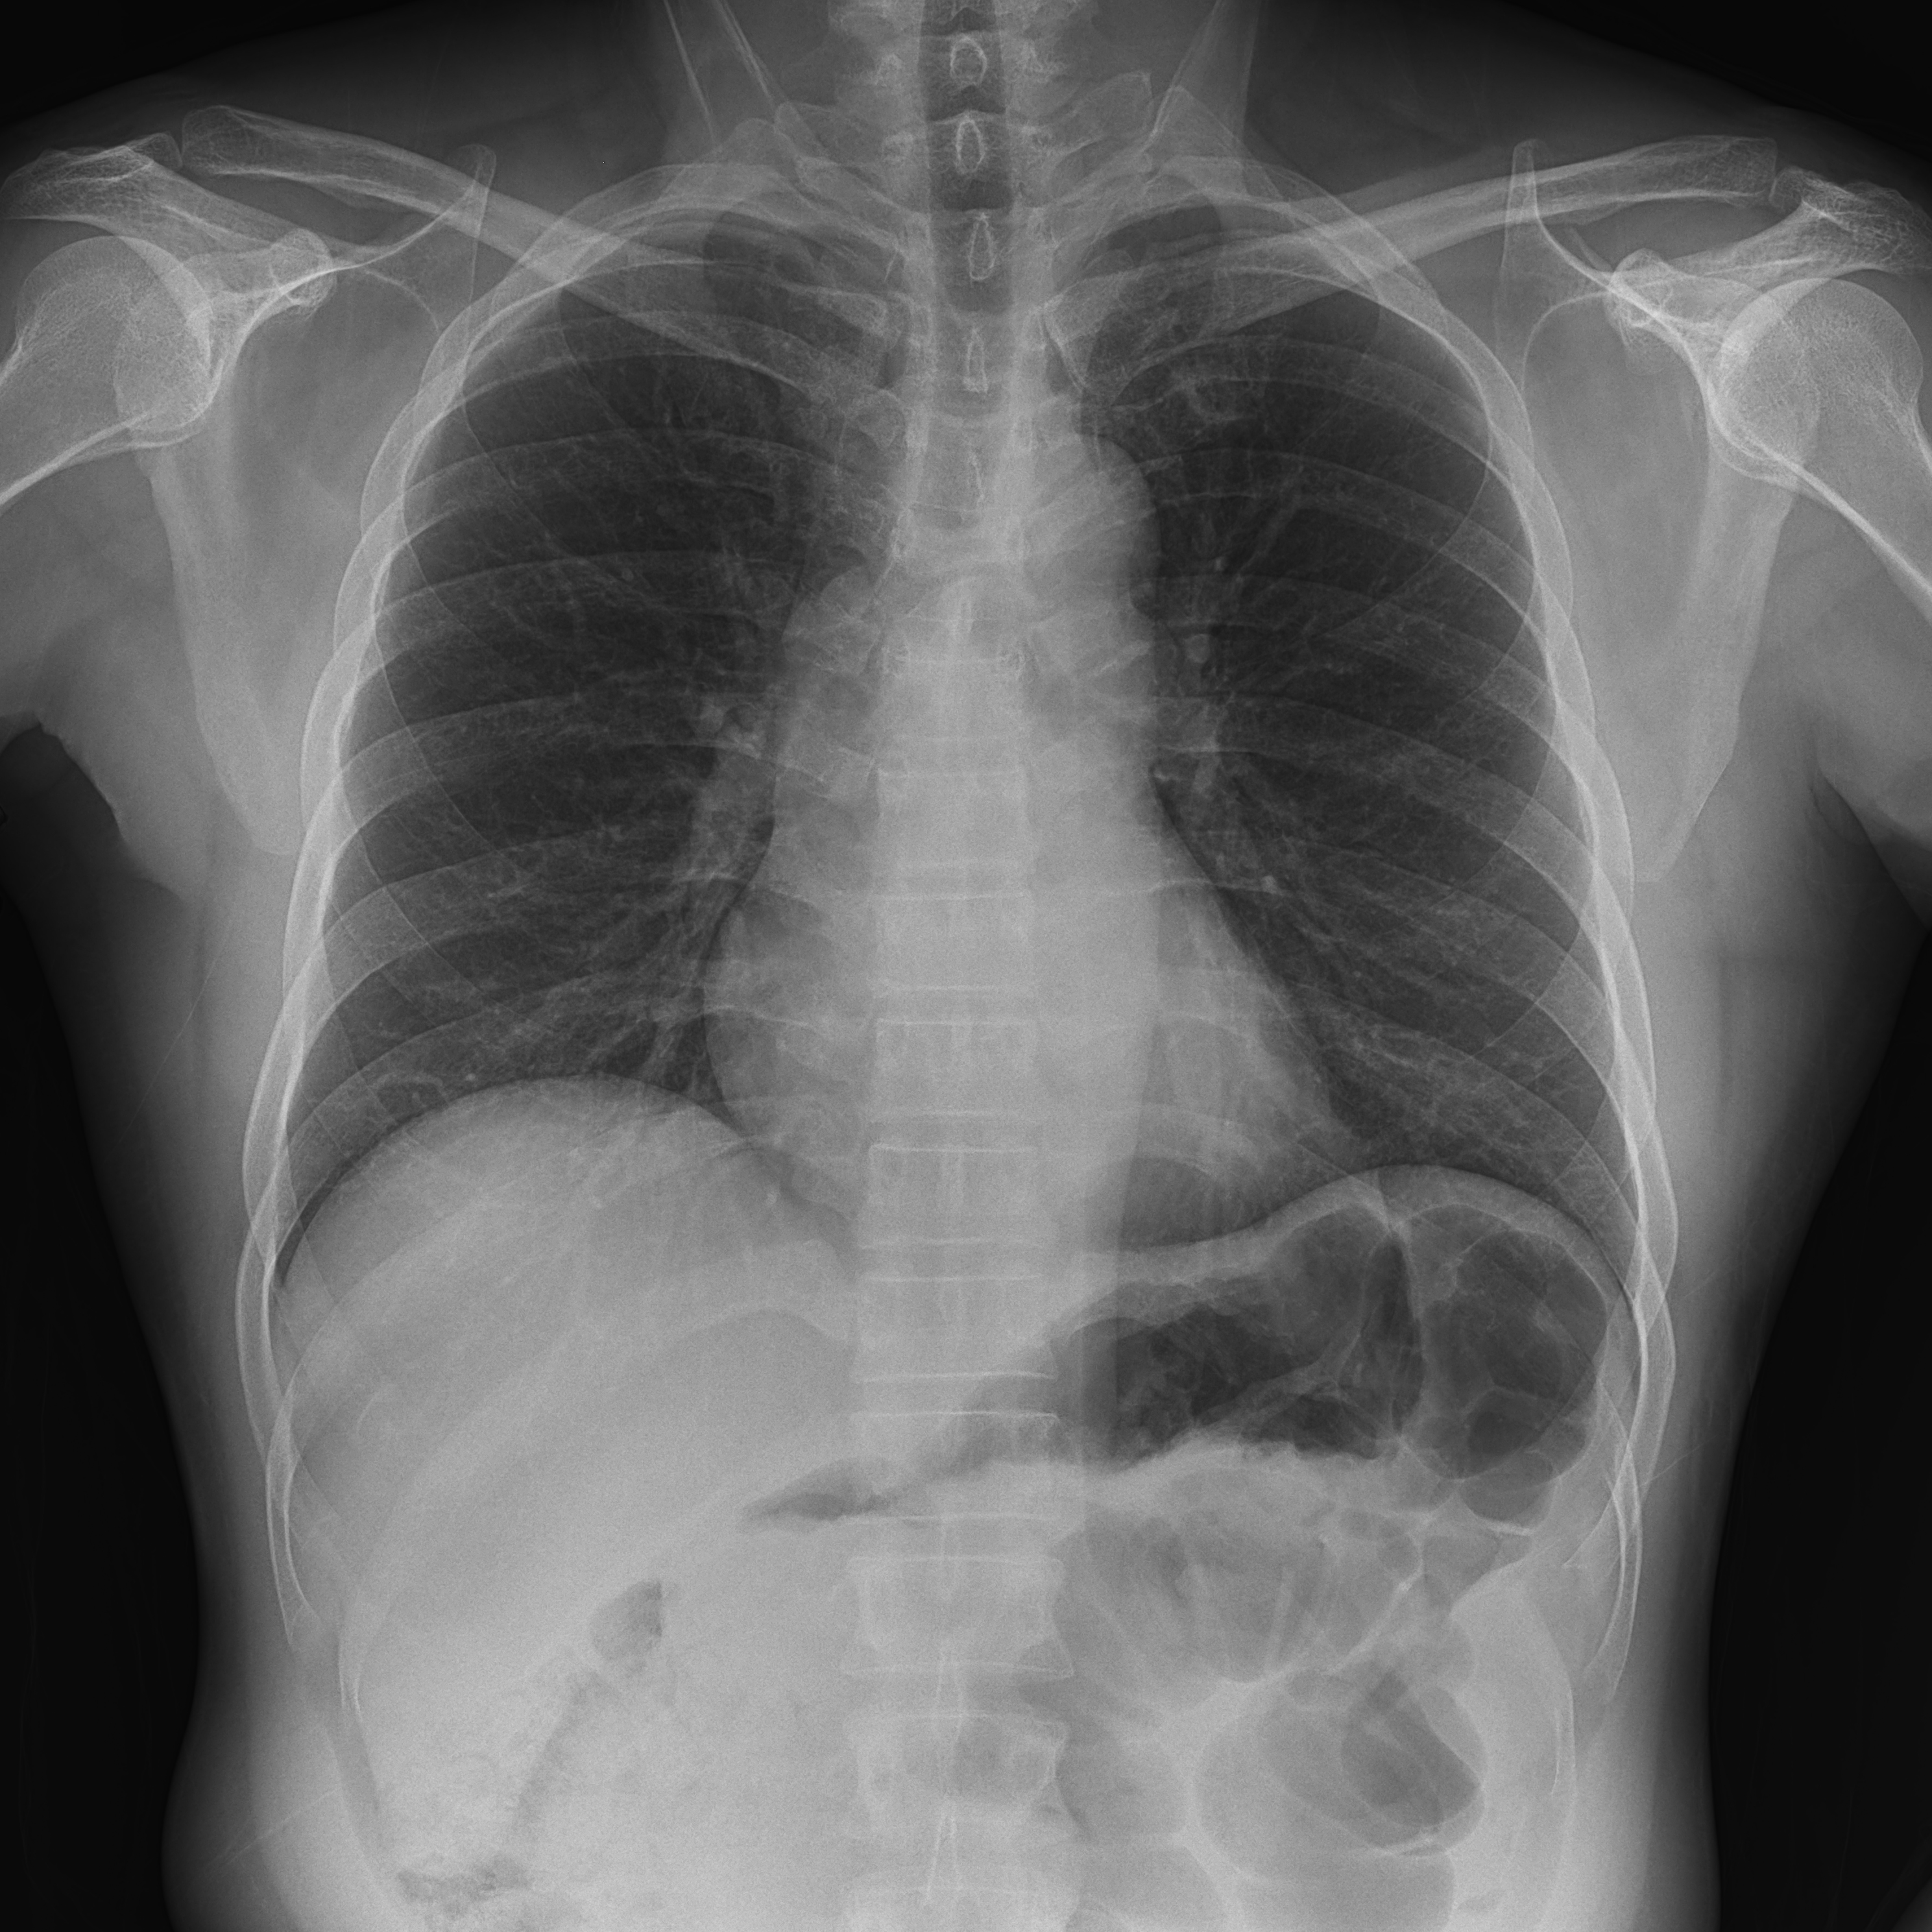

临床图片